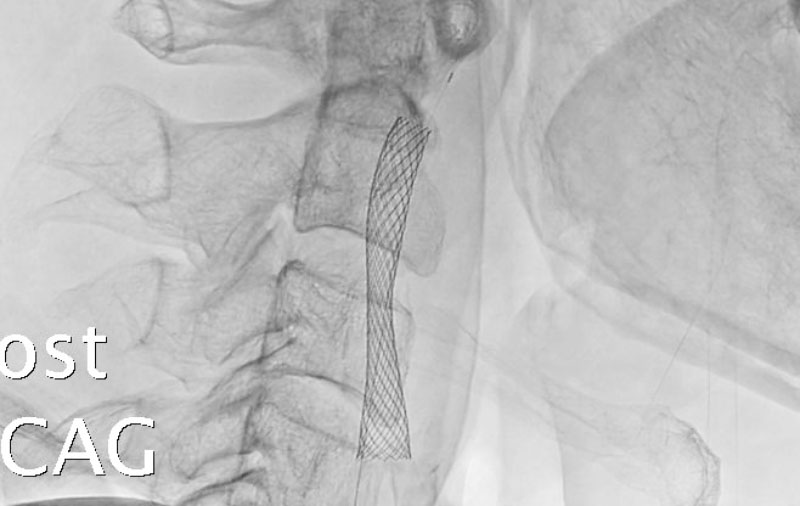

解離性脳底動脈瘤破裂

50代

大阪府の病院

No.1470 手術前

No.1470 手術中

No.1470 手術後